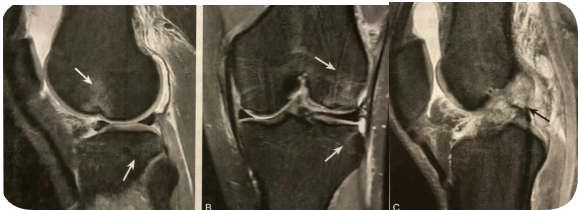

阅片要点:

1. 半月板桶柄状撕裂的间接征象;诊断敏感性不高,特异性较高;

2. 在 MRI 脂肪序列上观察最佳,冠状位或矢状位均可;冠状位最佳,注意区分前、后交叉韧带结构;

3. MRI 注意观察伴发的前、后交叉韧带损伤。